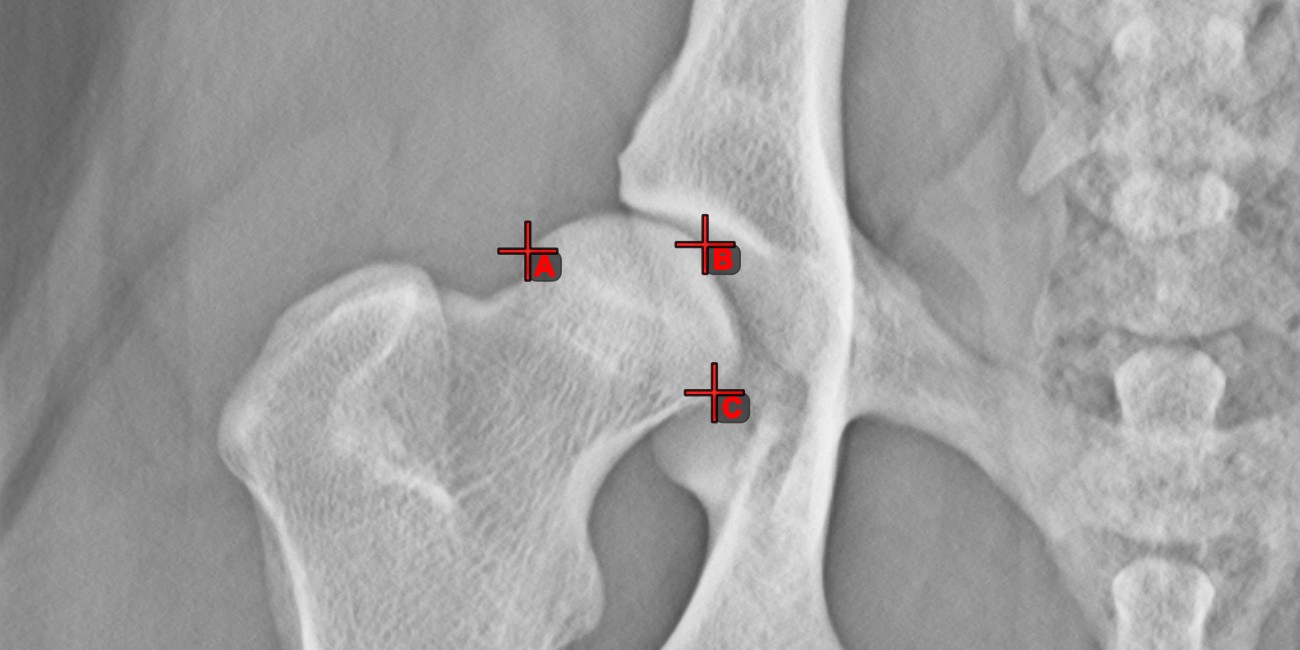

Messpunkt¶

Measurement Point

. Jeder Punkt ist zur besseren Identifizierung mit einem Buchstaben versehen.Objekt auswählen/verschieben

. Wählen Sie den Punkt mit der zugewiesenen Maustaste des Werkzeugs aus und verschieben Sie ihn dann frei an eine beliebige Stelle im Bild.